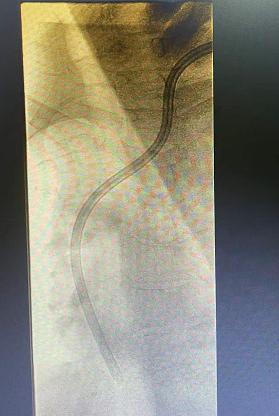

王女士,确诊尿毒症7+年时间,长期依靠左侧cuff导管行血液透析治疗,因确诊导管感染,经过反复治疗后效果不佳,所以必须拔除维持患者生命的唯一的血管通路,但是血管通路是尿毒症患者维持生存的必备条件,目前患者又处于病危状态、高钾、水负荷重,心衰明显,必须立即建立新的血管通路行血液透析治疗去维持生命,由于患者自身血管条件差,动静脉内瘘建立困难,临时血管通路建立难度极大,临时安置股静脉导管、颈内静脉导管均失败,不能满足血液透析要求,对此,患者悲痛欲绝、陷入绝望,家属也不放弃任何能够救治的机会,啃啃哀求郑医生能够为患者开辟一条“活路”;于是肾病科主任毕伟红、副主任王婷立刻紧急召开血管通路小组会议,由于王女士基础疾病多且复杂,DSA下造影显示左侧头臂静脉重度狭窄伴血栓形成,手术难度及风险极大,经过讨论,主刀医生郑星和张艳玲医生快速为患者量身定制手术方案,决定联合运用介入技术(DSA)+PTA技术,为王女士开辟一条新的“活路”。王女士,确诊尿毒症7+年时间,长期依靠左侧cuff导管行血液透析治疗,因确诊导管感染,经过反复治疗后效果不佳,所以必须拔除维持患者生命的唯一的血管通路,但是血管通路是尿毒症患者维持生存的必备条件,目前患者又处于病危状态、高钾、水负荷重,心衰明显,必须立即建立新的血管通路行血液透析治疗去维持生命,由于患者自身血管条件差,动静脉内瘘建立困难,临时血管通路建立难度极大,临时安置股静脉导管、颈内静脉导管均失败,不能满足血液透析要求,对此,患者悲痛欲绝、陷入绝望,家属也不放弃任何能够救治的机会,啃啃哀求郑医生能够为患者开辟一条“活路”;于是肾病科主任毕伟红、副主任王婷立刻紧急召开血管通路小组会议,由于王女士基础疾病多且复杂,DSA下造影显示左侧头臂静脉重度狭窄伴血栓形成,手术难度及风险极大,经过讨论,主刀医生郑星和张艳玲医生快速为患者量身定制手术方案,决定联合运用介入技术(DSA)+PTA技术,为王女士开辟一条新的“活路”。王女士,确诊尿毒症7+年时间,长期依靠左侧cuff导管行血液透析治疗,因确诊导管感染,经过反复治疗后效果不佳,所以必须拔除维持患者生命的唯一的血管通路,但是血管通路是尿毒症患者维持生存的必备条件,目前患者又处于病危状态、高钾、水负荷重,心衰明显,必须立即建立新的血管通路行血液透析治疗去维持生命,由于患者自身血管条件差,动静脉内瘘建立困难,临时血管通路建立难度极大,临时安置股静脉导管、颈内静脉导管均失败,不能满足血液透析要求,对此,患者悲痛欲绝、陷入绝望,家属也不放弃任何能够救治的机会,啃啃哀求郑医生能够为患者开辟一条“活路”;于是肾病科主任毕伟红、副主任王婷立刻紧急召开血管通路小组会议,由于王女士基础疾病多且复杂,DSA下造影显示左侧头臂静脉重度狭窄伴血栓形成,手术难度及风险极大,经过讨论,主刀医生郑星和张艳玲医生快速为患者量身定制手术方案,决定联合运用介入技术(DSA)+PTA技术,为王女士开辟一条新的“活路”。郑星医生表示在:介入技术能够快速发现患者血管通路问题所在,能让“隐形”的血管可视化,精准定位,提高手术操作成功率;由于王女士左侧头臂静脉重度狭窄伴血栓形成,导管通过狭窄部位困难,然而利用PTA技术能够扩张血管重度狭窄部位,让导管顺利通过,两种技术联合运用,极大地降低手术风险,减少了患者的痛苦。生命线的顺利重置,血液透析治疗的顺利开展,让患者及家属顿时喜笑颜开,重燃了患者生存的希望。

(术前) (术前) (术后)

经皮血管腔内血管成形术(PTA):通过经皮穿刺血管,置入导丝,沿导丝将球囊输送至血管狭窄病变处,将扩张球囊送入血管狭窄部位并对其进行扩张,从而将狭窄血管矫正至正常血管内径。